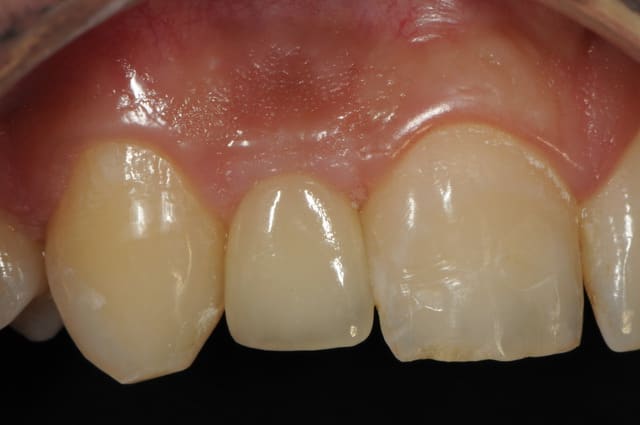

01/09/2010 à 16h54

-1 ou 2 mois plus tard ( je sais plus)

- empreinte avec transfert pop in

- pilier zircone esthétique Axiom

- prothèse et pilier

- pilier zircone en place

- couronne en place (petite compression gingivale)

fin du traitement